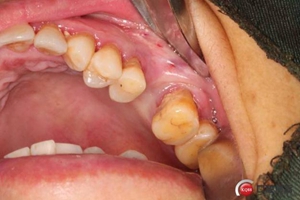

改良式外提升工具盒-外提 科貿(mào)嘉友收錄

大家好,我是梁老師的助理小依。由于梁老師每天手術(shù)檔期安排較滿,加上經(jīng)常出差講課,沒有時(shí)間整理病例 。為了方便大家更及時(shí)的了解梁老師最新手術(shù)動(dòng)態(tài),以后將由我為大家整理并推送梁老師最新經(jīng)典案例。案例文字旁白少,但圖片會(huì)盡量完整展示手術(shù)全過程,供大家學(xué)習(xí)參考。有任何問題,可以留言,梁老師會(huì)親自為大家解答。感謝大家對梁老師的支持和關(guān)注!